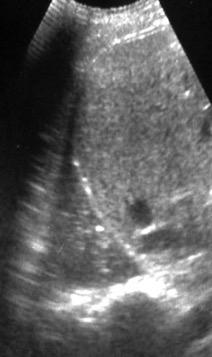

Patrón ecográfico de empiema

Anecoico.....0%. (0 de 47)

Complejo no septado no hiperecoico... ……………..0% (0 de 36)

Complejo, no septado hiperecoico......100% (2/2)

Complejo septado …35% (11 de 31)

Ecogénico homogéneo .... 100% (2 de 2)

Wang T et al. Value of ultrasonography in determining the nature of pleural effusion. Analysis of 582 cases. Medicine 2022.

Chih-Yen Tu et al. Chest Ultrasound Study Pleural Effusions in Febrile Medical ICU. Chest 2004